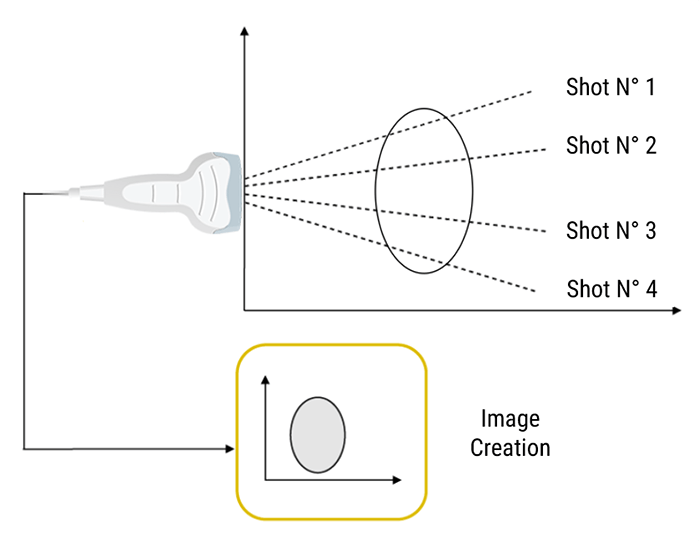

Scanning Technique

However, It is sufficient to perform a large number of different ultrasound shots by shifting the firing axis each time. The position of a point on the screen depends on the flight time of the echo and the position of the corresponding ultrasonic firing axis.

Sequence of Ultrasound Shots

What is Pulse Repetition Frequency? And what does it depend on?

Pulse Repetition Frequency (PRF) is the number of ultrasound pulses emitted by the transducer per second. It depends on the speed of sound and the depth of exploration; Thus it can be altered by changing the depth of imaging. The further the ultrasound travels into the tissue, the higher the PRF becomes.